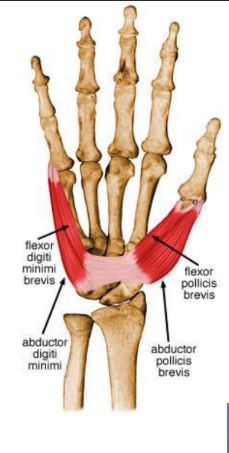

Four thenar muscles

Abductor pollicis brevis

Flexor pollicis brevis

Opponens pollicis brevis

Adductor pollicis brevis

Four hypothenar muscles

Palmaris brevis

Abductor digiti minimi

Flexor digiti minimi

Oppenens digiti minimi

Thenar muscles

ORIGIN | INSERTION | ACTION | INNERVATION | |

Abductor pollicis brevis | Flexor retinaculum and tubercle of scaphoid and crest of trapezium | Lateral of base of proximal phalanx of thumb | Abducts the thumb at metacarpophalangeal and carpometacarpal joint | Median nerve |

Flexor pollicis brevis | Superficial head- flexor retinaculum and crest of trapezium Deep- trapezoid and capitate bone | Lateral side of base of proximal phalanx | Flexes thumb | Median nerve |

Opponens pollicis | Flexor retinaculum and crest of trapezium | Lateral side of 1st metacarpal | Draws 1st metacarpal to oppose thumb | Median nerve |

Adductor pollicis | Oblique- base of 2nd and 4rd metacarpals, capitate and adjacent carpals Transverse- palmar surface of 3rd metacarpal | Medial side of base of proximal phalanx of thumb | Muscle adducts thumb from flexed or abducted position | Deep branch of ulnar nerve |

Hypothenar muscles

ORIGIN | INSERTION | ACTION | INNERVATION | |

Abductor digiti minimi | Pisiform bone | Medial side of base of proximal phalanx of little finger | Abducts little finger | Deep branch of ulnar nerve |

Flexor digiti minimi | Hook of hamate a/nd flexor retinaculum | Medial side of base of proximal phalanx of little finger | Flexes little finger at metacarpophalangeal joint | Deep branch of ulnar nerve |

Opponens digiti minimi | Hook of hamate and flexor retinaculum | Medial border of shaft of 5th metacarpal | Draws 5th metacarpal anteriorly and rotates it laterally, opposes thumb | Deep branch of ulnar nerve |

Palmaris brevis | Flexor retinaculum and palmar aponeurosis | Skin along medial border of hand | Helps with gripping | Superficial branch of ulnar nerve |